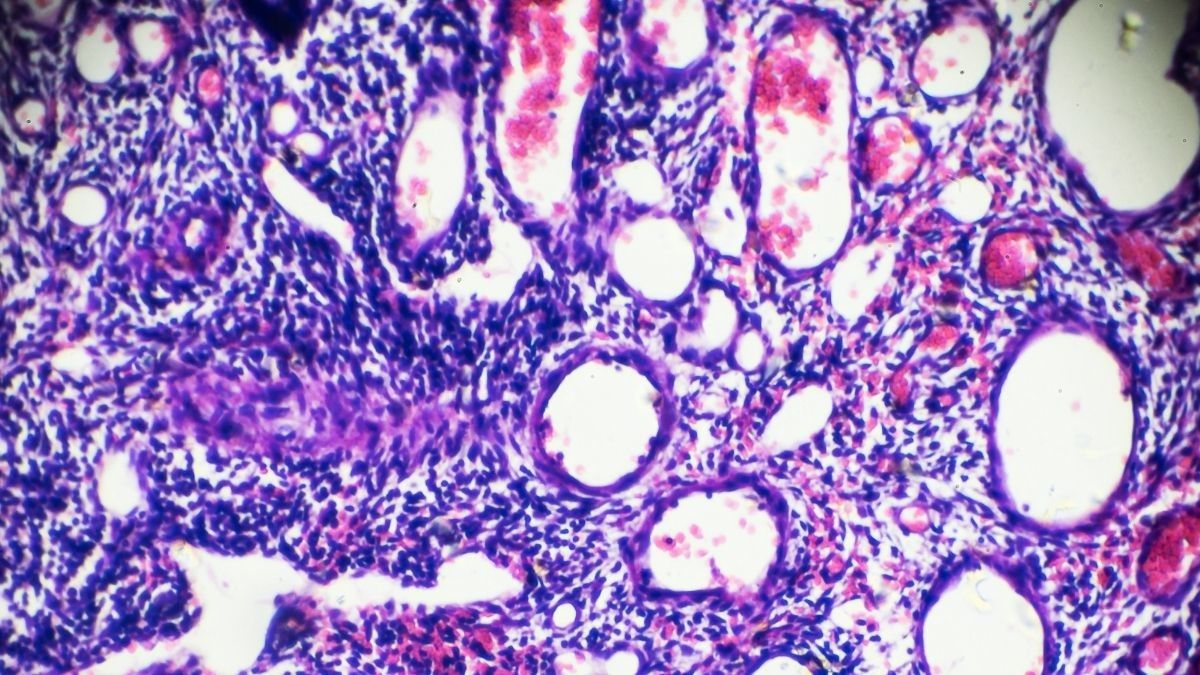

Polip rahim adalah suatu benjolan yang melekat pada dinding rahim bagian dalam. Penyakit yang punya nama medis polip endometrium ini terjadi akibat munculnya tumor atau benjolan yang mengarah ke dalam rongga rahim.

Tindakan ini dilakukan dengan mengambil jaringan pada dinding rahim (endometrium) untuk nantinya diperiksa lebih lanjut di laboratorium.

Adapun penanganan lain yang mungkin dilakukan, yaitu pembedahan. Tindakan ini bertujuan untuk mengangkat polip untuk nantinya diperiksa lebih lanjut di laboratorium. Apabila polip tersebut menunjukkan tanda adanya sel-sel kanker, maka dokter akan melakukan penanganan lebih lanjut.

Sesuai namanya, polip serviks adalah tumor yang tumbuh di area leher rahim (serviks). Para pakar kesehatan menduga bahwa penyakit ini berhubungan dengan adanya peningkatan hormon estrogen atau peradangan jangka panjang pada vagina, leher rahim, atau organ rahim itu sendiri.